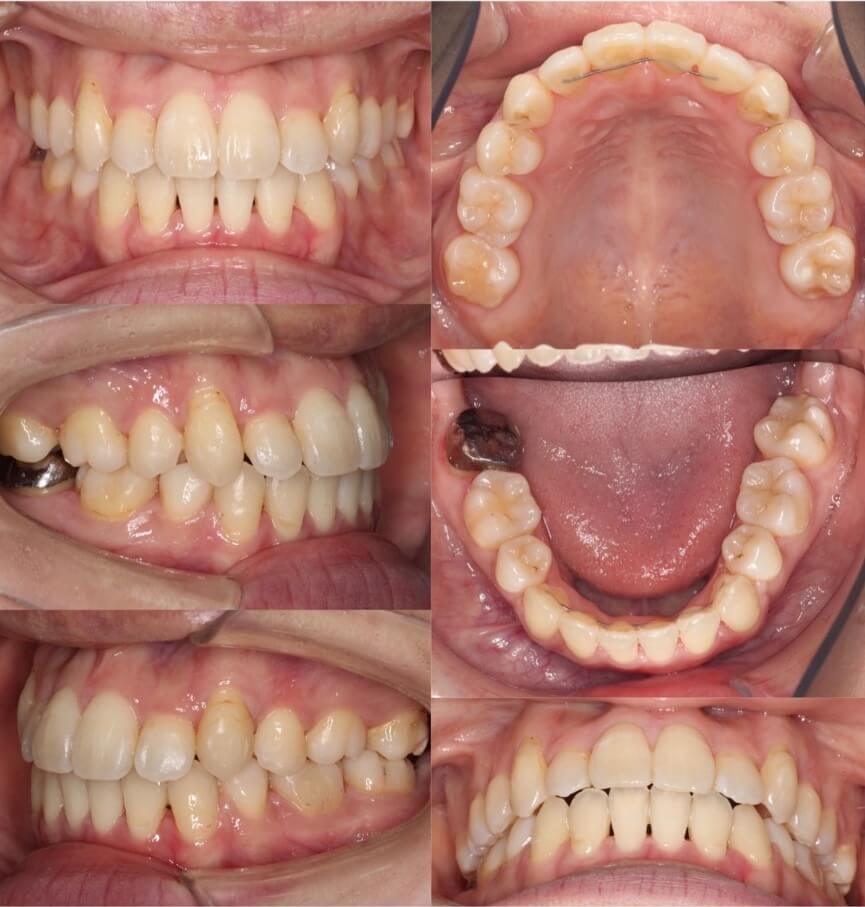

20代女性・唇側矯正装置・上下抜歯

八重歯があり上の歯並びに強いがたつきがある受け口ケースです。反対咬合で小臼歯を抜歯する際は上は5番を抜歯することが多いです。これは、上の前歯を後ろに引きすぎないようにするためです。下の歯並びには前歯の後方移動を効率化するために、2本ワイヤーを使用しています。

<症例概要> 難易度 ★★★★☆

主訴:受け口・前歯のガタガタ

年齢・性別:大学生女性

住まい:千葉県八千代市

症状:反対咬合・重度叢生

治療方針:上下小臼歯抜歯・上顎歯列拡大・空隙閉鎖

治療装置:唇側矯正装置

固定装置:上リンガルアーチ・III級顎間ゴム

抜歯:上第二小臼歯・下第一小臼歯(計4本)

治療期間:2年3か月

リテーナー:上下フィックスタイプ+プレートタイプ

治療費用:990,000(税込)

代表的副作用:痛み・治療後の後戻り・歯根吸収・歯髄壊死・歯肉退縮